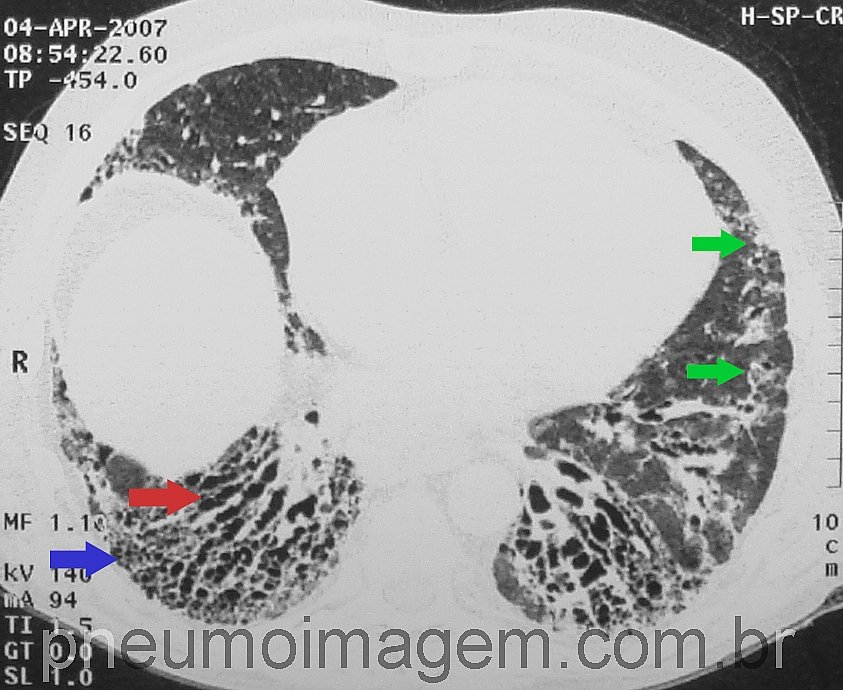

DESTAQUES DO ERS2016: FIBROSE PULMONAR IDIOPÁTICA ASSOCIADA AO ENFISEMA PULMONARA presença de mais de 15% de enfisema na TC de tórax impacta a variação da CVF no ano seguinte e isso pode ser um critério diagnóstico para a síndrome de associação entre FPI e enfisema. Múltiplos cistos grandes, diferentes do padrão em favo de mel, são característicos dessa associação.

Enfisema é frequente em pacientes com doença intersticial relacionada à Esclerose Sistêmica, até mesmo em não fumantes. Há algumas formas genéticas de associação entre enfisema e FPI.